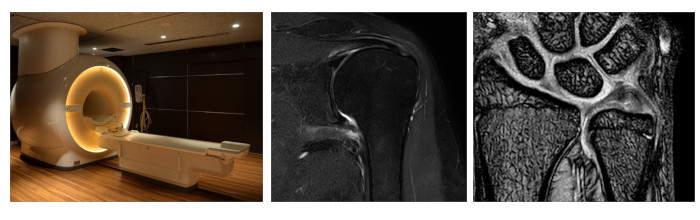

MRIとはMagnetic Resonance Imaging(磁気共鳴画像)の略で、強力な磁場と電波を使って、人体の任意方向の断面撮像が可能な装置です。

当院ではPHILIPS社製の磁場強度1.5T(テラス)のMRI装置が2台稼働しています。X線を使用しないため放射線による被ばくもなく、脊椎や関節など詳細に撮影できます。また、造影剤を使用せずに脳血管などの血管の情報を得ることが出来ます。

検査中は道路工事に似た様な大きな音がしますが、痛み等はありません。検査時間は検査部位によって異なりますが、20分~30分ほどです。

撮影室内は強力な磁場が発生しています。体内に金属があると撮像できない場合がありますので、検査前に確認をさせていただきます。

当院MR装置 PHILIPS MRI Ingenia 1.5T